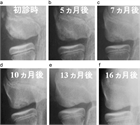

1. 主な症状は疼痛であるが、離断性骨軟骨炎の病初期では症状が乏しいことの記載に関する文献を変更した(Matsuura T, et al. JSES Int. 2024 Feb;8(3):661-666.)。

1. 離断性骨軟骨炎について症状が乏しい症例の発見には超音波検査が有用であることを記載した。